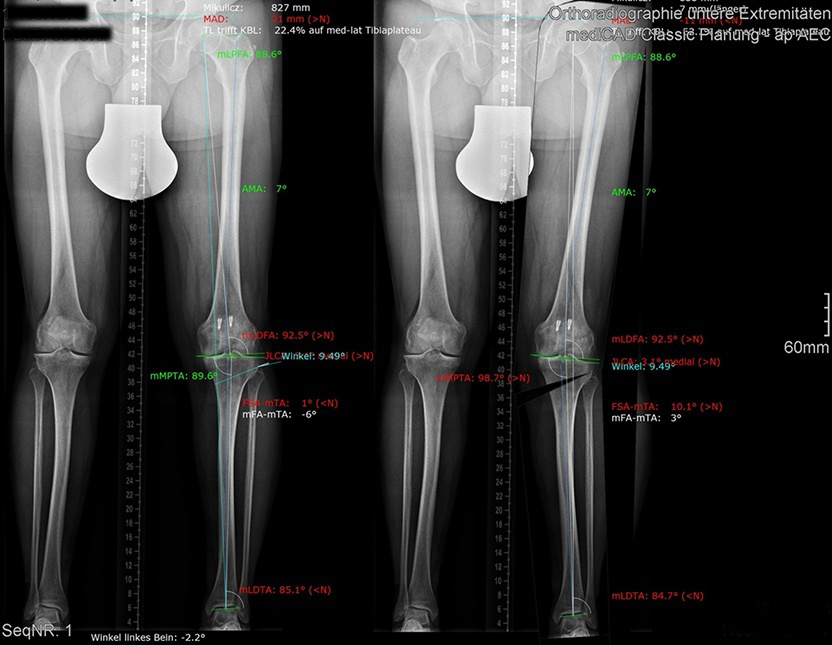

Dr. med. Alexander Strehl: Bei einer Umstellungsosteotomie wird die Lastachse im Knie und somit auch auf den Knorpel korrigiert. Korrekterweise geht die Belastung vom Oberschenkelkopfzentrum zum Sprunggelenkszentrum etwa mittig durchs Knie. Bei O- oder X-Beinen weicht diese Achse ab. Dies kann aus unterschiedlichen Gründen sein, zum Beispiel durch einen früheren Beinbruch oder weil der Patient in der Zeit des Skelettwachstums viel Fussball gespielt hat, kommt aber auch oft ohne eigentliche Ursache vor. Das O-Bein ist häufiger als das X-Bein. Manchmal sieht man diese Abweichung der Beinachse nicht auf den ersten Blick, sondern erst mit einer Ganzbeinstandaufnahme.

Durch O- oder X-Beine wird der Knorpel im Knie einseitig belastet. Da reichen manchmal schon wenige Millimeter, die die Achse abweicht. Folge ist, dass sich eine Knorpelseite deutlich schneller abnutzt als die andere. Mit der Operation wird die Belastung zurück auf die Mitte gesetzt oder eine kleine Überkorrektur auf die gesunde Seite vollzogen, sodass diese etwas mehr belastet und die abgenutztere Seite entlastet wird.

Und was geschieht bei der Operation, damit diese Korrektur erreicht wird?

Dr. med. Alexander Strehl: Bei der häufigsten Umstellungsosteotomie am Unterschenkelkopf macht man einen Sägeschnitt am Knochen, klappt diesen gezielt auf und fixiert ihn mit einer winkelstabilen Platte; dies auf Basis dessen, was man vor der Operation bei der Planung gemessen und errechnet hat. Es entsteht ein winkelförmiger Spalt im Knochen, der von selber wieder zuwächst. Je nach Ort und Art der Deformität findet auch der Eingriff statt. Bei einem O-Bein ist dies meistens am Unterschenkelkopf. Es können aber auch Eingriffe am Oberschenkel nötig sein, vor allem beim X-Bein. Bei extremen Deformitäten kann auch eine Doppelosteotomie erforderlich sein, also dass man am Ober- und Unterschenkel korrigieren muss, um wieder eine gerade Achse zu erhalten. Dies muss man im Vorfeld genau analysieren und planen. Während der Operation wird die Beinachse mehrfach mit dem Ausrichtestab überprüft.